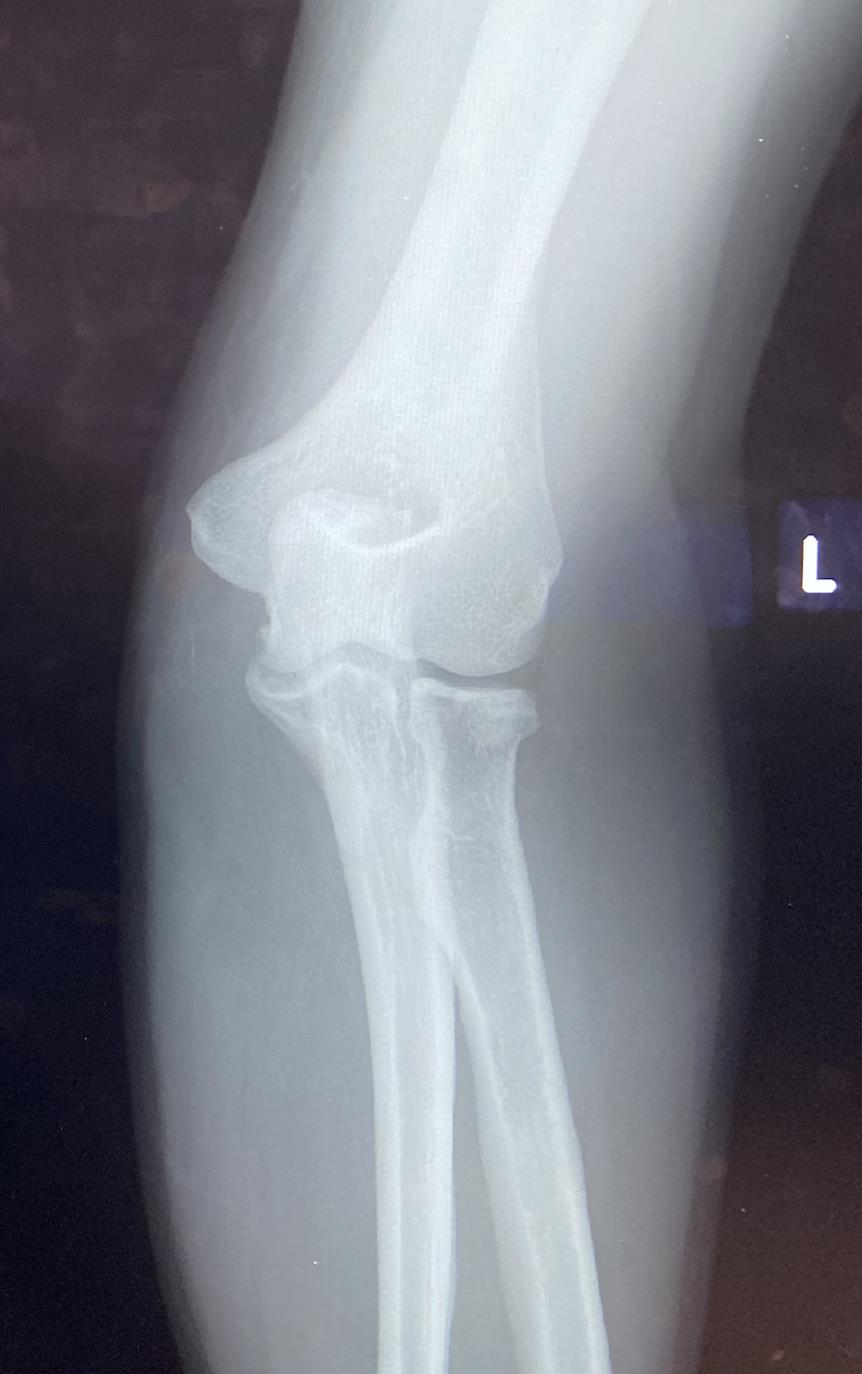

• Radial Head Fractures are common intra-articular elbow fractures that can be associated with an episode of elbow instability, a mechanical block to elbow motion, an injury to the distal radioulnar joint and/or to the interosseous membrane (Essex-Lopresti).

• Diagnosis can be made with plain radiographs of the elbow. CT studies can be helpful for surgical planning.

• Radiographs

• recommended views

• AP and lateral elbow

• AP and lateral forearm/wrist

• additional views

• radiocapitellar view (Greenspan view)

• oblique lateral view of elbow

• beam angled 45 degrees cephalad

• allows visualization of the radial head without coronoid overlap

• helps detect subtle fractures of the radial head

• findings

• fracture with or without displacement/intra-articular involvement

• may see anterior/posterior fat pad sign indicating occult minimally displaced fracture

• demonstrates intra-articular hemarthrosis

• posterior fat pad sign more sensitive for fracture

• must rule out concomitant involvement of forearm/wrist